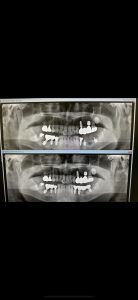

次はI.O.Dのメタルアップセット

変なエステ義歯から‥

遡りblog参照下さい